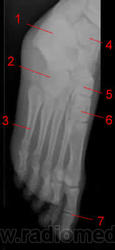

Стопа.

1, Пяточная кость.

2, Кубовидная кость.

3, Пятая плюсневая кость.

4, Таранная кость.

5, Ладьевидная кость.

6, Клиновидная кость.

7, Межфаланговый сустав.